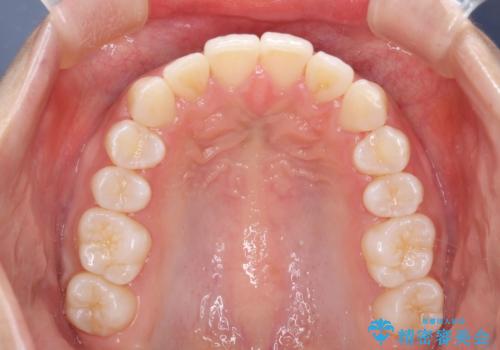

Invisalign インビザラインによる軽度なガタつきの改善